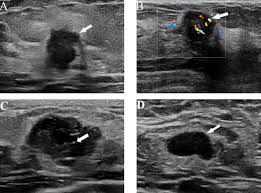

It's called inflammatory because that's how it looks. Any area that does not look like normal tissue is a possible cause for concern. Inflammatory breast cancer, also known as carcinomatous mastitis, t4d, or pev 2 or 3, is the only real therapeutic emergency in breast oncology, given the high risk of metastasis, the reason for the most unfavourable prognosis of all breast cancers.it must consequently be diagnosed rapidly, and imaging examinations must in no case delay therapeutic management. Because ibc grows quickly, it is usually found at a locally advanced stage, meaning that cancer cells have spread into nearby breast tissue or lymph nodes. A breast ultrasound is a scan that uses penetrating sound waves that do not affect or damage the tissue and cannot be heard by humans. Ultrasound is useful for looking at some breast changes, such as lumps (especially those that can be felt but not seen on a mammogram) or changes in women with dense breast tissue. As these inflammatory breast cancer picture shows, the texture of the breast may change and appear to look dimpled or ridged, like an orange peel. Their differences, however, lie in their enhancement.

However, inflammatory breast cancers are more likely to show solid mass lesions. The problem is that inflammatory breast cancer can look very much like mastitis early on, and is often diagnosed only after a woman has been treated first for mastitis (often with no improvement in symptoms). This condition usually does not develop a lump, but commonly affects the breast skin. The aim of this study was to evaluate the features of inflammatory breast carcinoma (ibc) on mri compared with mammography and ultrasound and to better define the role of mri in patients with this aggressive disease. These tubes, which are hollow, allow lymph fluid to drain out of the breast.

Rapid onset of symptoms (redness, swelling, warmth, itching, skin thickening) are hallmarks of the disease. You can imagine my fear when a red area appeared on my chest. Early warning signs of inflammatory breast cancer along with images of inflammatory breast cancer are mentioned below. However, inflammatory breast cancers are more likely to show solid mass lesions. The aim of this study was to evaluate the features of inflammatory breast carcinoma (ibc) on mri compared with mammography and ultrasound and to better define the role of mri in patients with this aggressive disease. I need some knowledge about ibc. My last breast ultrasound was december. I know imaging doesn't show ibc.

Most inflammatory breast cancers are invasive ductal carcinomas, which means. Inflammatory breast cancer accounts for between 1% and 5% of breast cancers and women do not usually have a lump and it doesn't usually. There is a pink area about the size of a quarter on the outside of my breast now for about a week with no change. Finding breast lumps and seeing change in the size and shape. Other ultrasound findings that suggest breast cancer include: This is referred to as peau d'orange, which is french for orange skin and it is caused by cancer cells blocking the lymph vessels beneath the skin, which have formed into ridges or tiny lumps. That indicates that the lesion likely contains a variety of elements, which may or may not indicate breast cancer. It often does not cause a breast lump, and it might not show up on a mammogram. In view of those symptoms often occur, and errors in diagnosis of patients treated for inflammatory diseases, that happen to be named and are known as these forms breast cancer. Ibc doesn't look like a typical breast cancer. This is a particularly aggressive cancer and i had chemo;bilateral mastectomy and radiotherapy ending at end of oct 09. I have inflammatory breast cancer which was firstly diagnosed as mastitis in jan 09. Learn more about ibc including the warning signs, diagnosis.